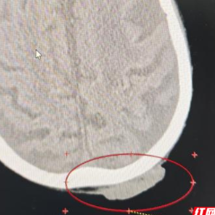

放射治疗前皮肤肿物。

放射治疗后皮肤减小。

肿瘤放射治疗团队为患者制定了详细、个体化的放疗治疗计划。经过40余的治疗,谭奶奶的疼痛日渐减轻,溃烂面逐渐缩小、愈合。更让她高兴的是整个治疗过程,没有出现呕吐和其他一些不良反应,食欲也没受太大影响,脸上也出现了往日的笑容。